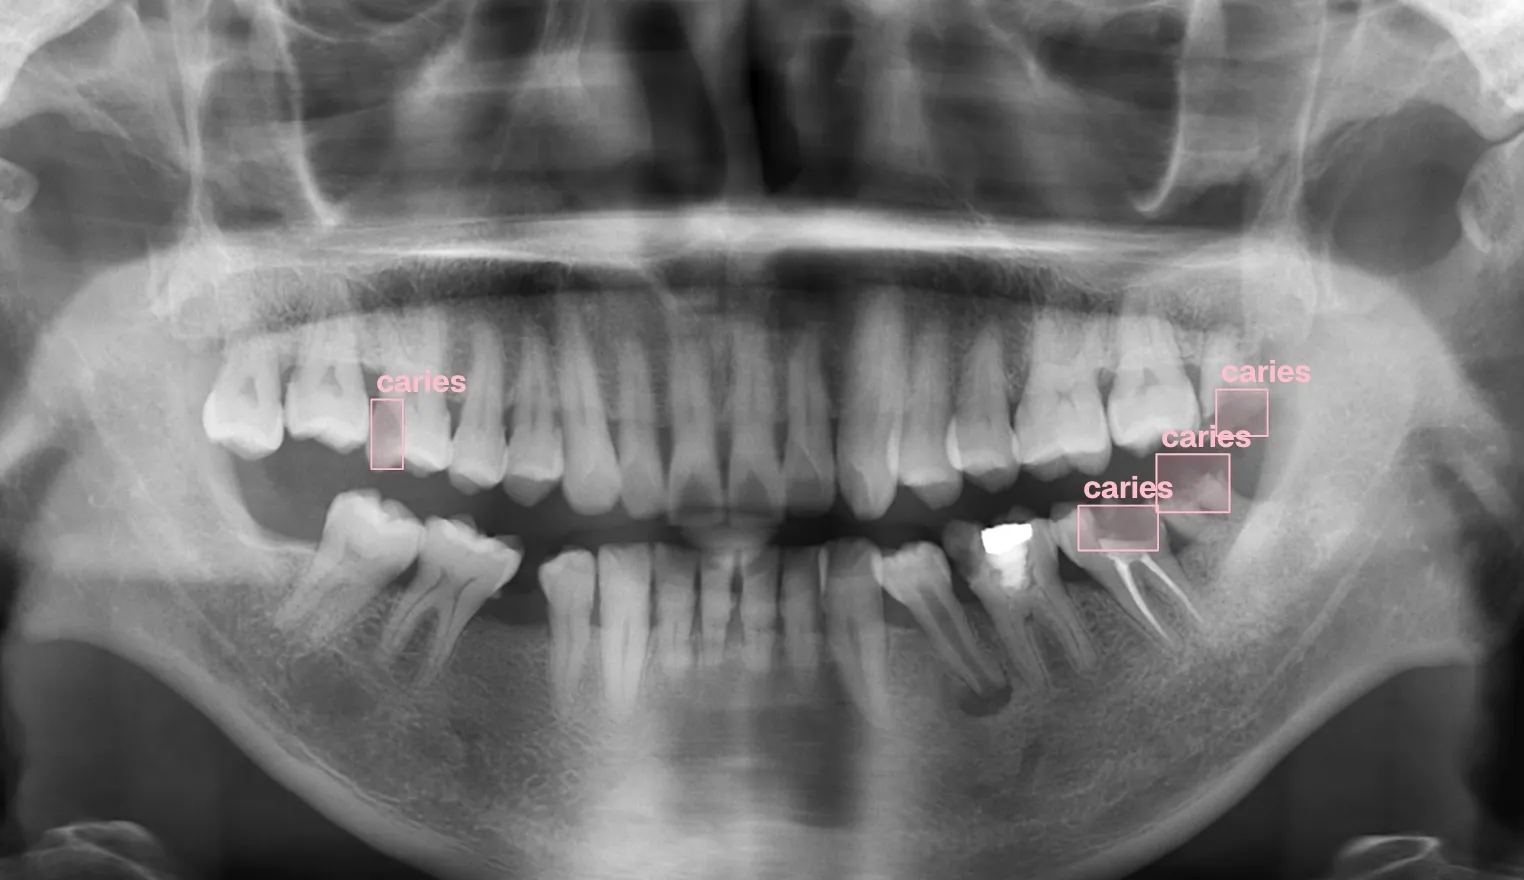

Building computer vision datasets and training YOLO models for automated dental pathology detection on panoramic X-rays.

- Identified caries patterns feeding AI dataset design

Annotating dental X-rays with clinician-grade precision for object detection and OBB tasks.